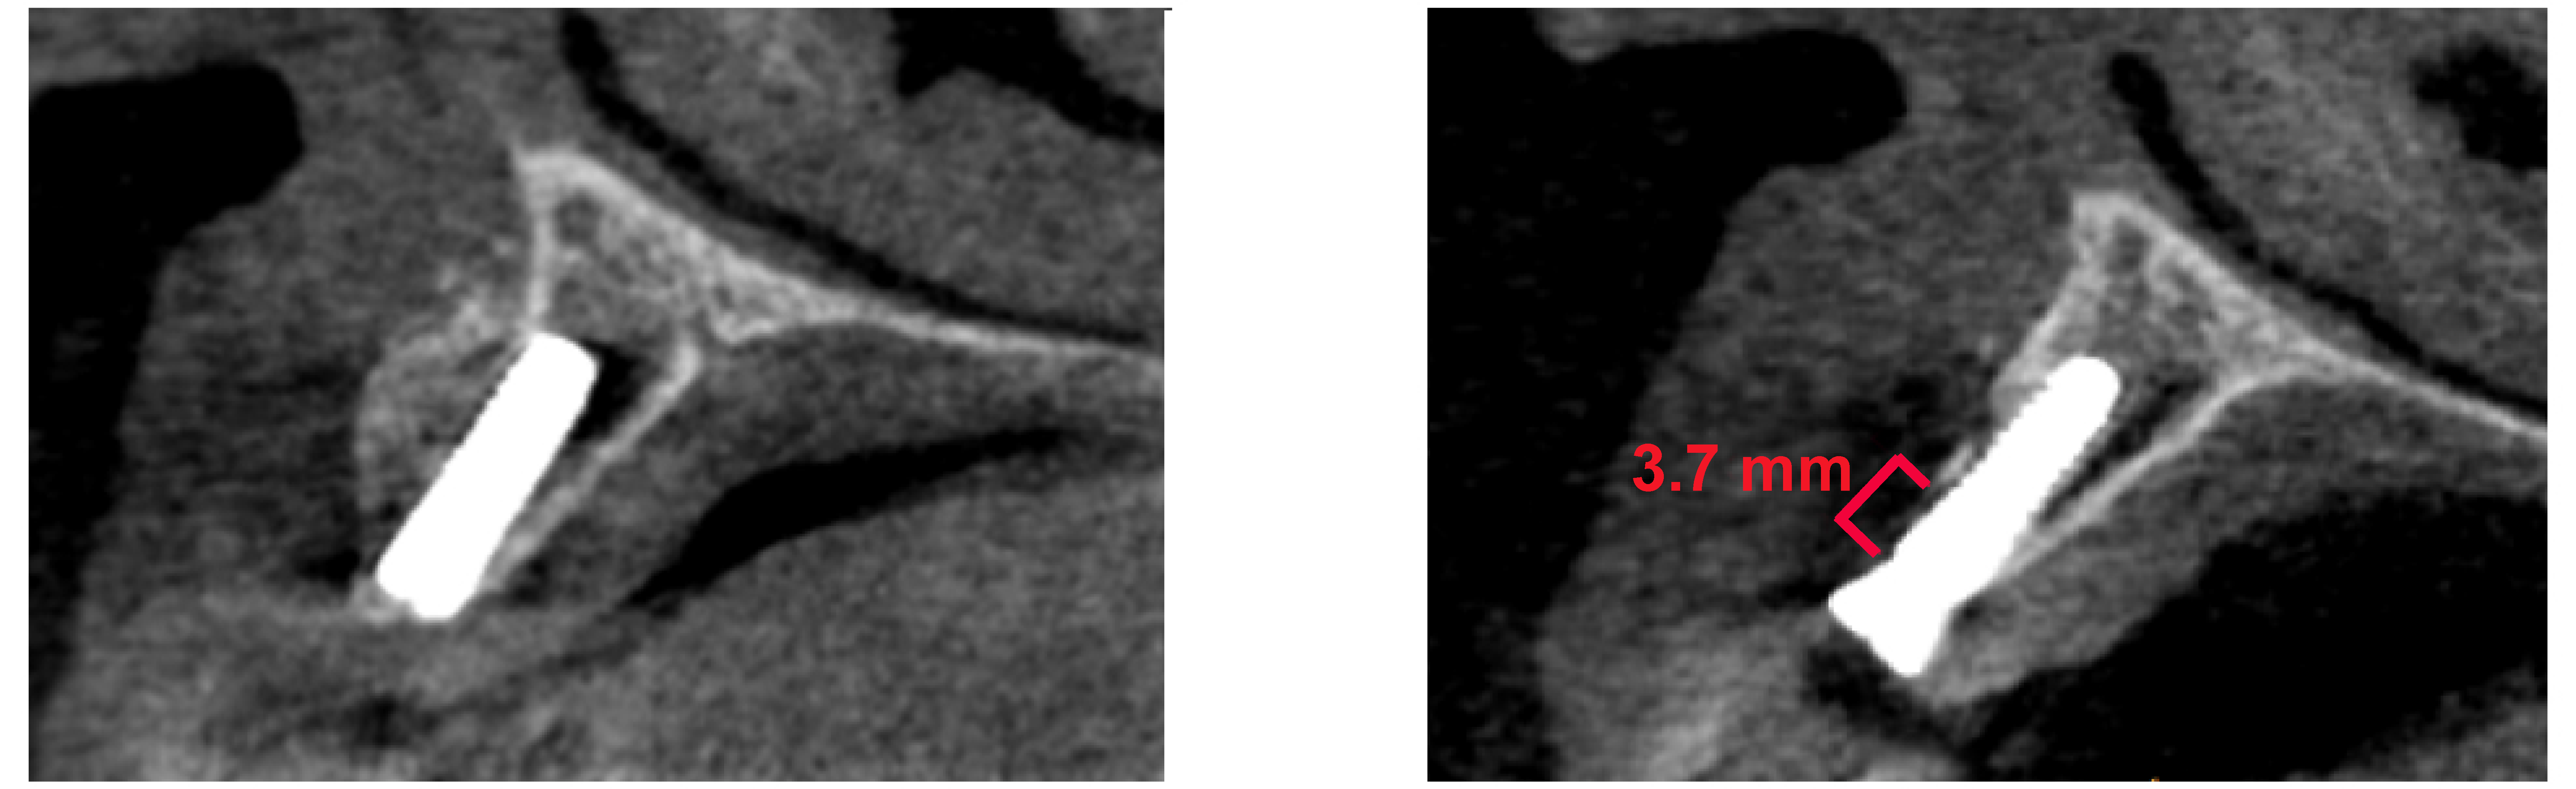

The radiological measurement was performed at the point of the most significant resorption. After accounting for lost implants, we retrospectively evaluated a radiological vertical bone loss exceeding 1 mm in the first year as the primary endpoint (Figure 3).

Figure 3.

3.7 mm vertical bone loss of buccal augmentation.